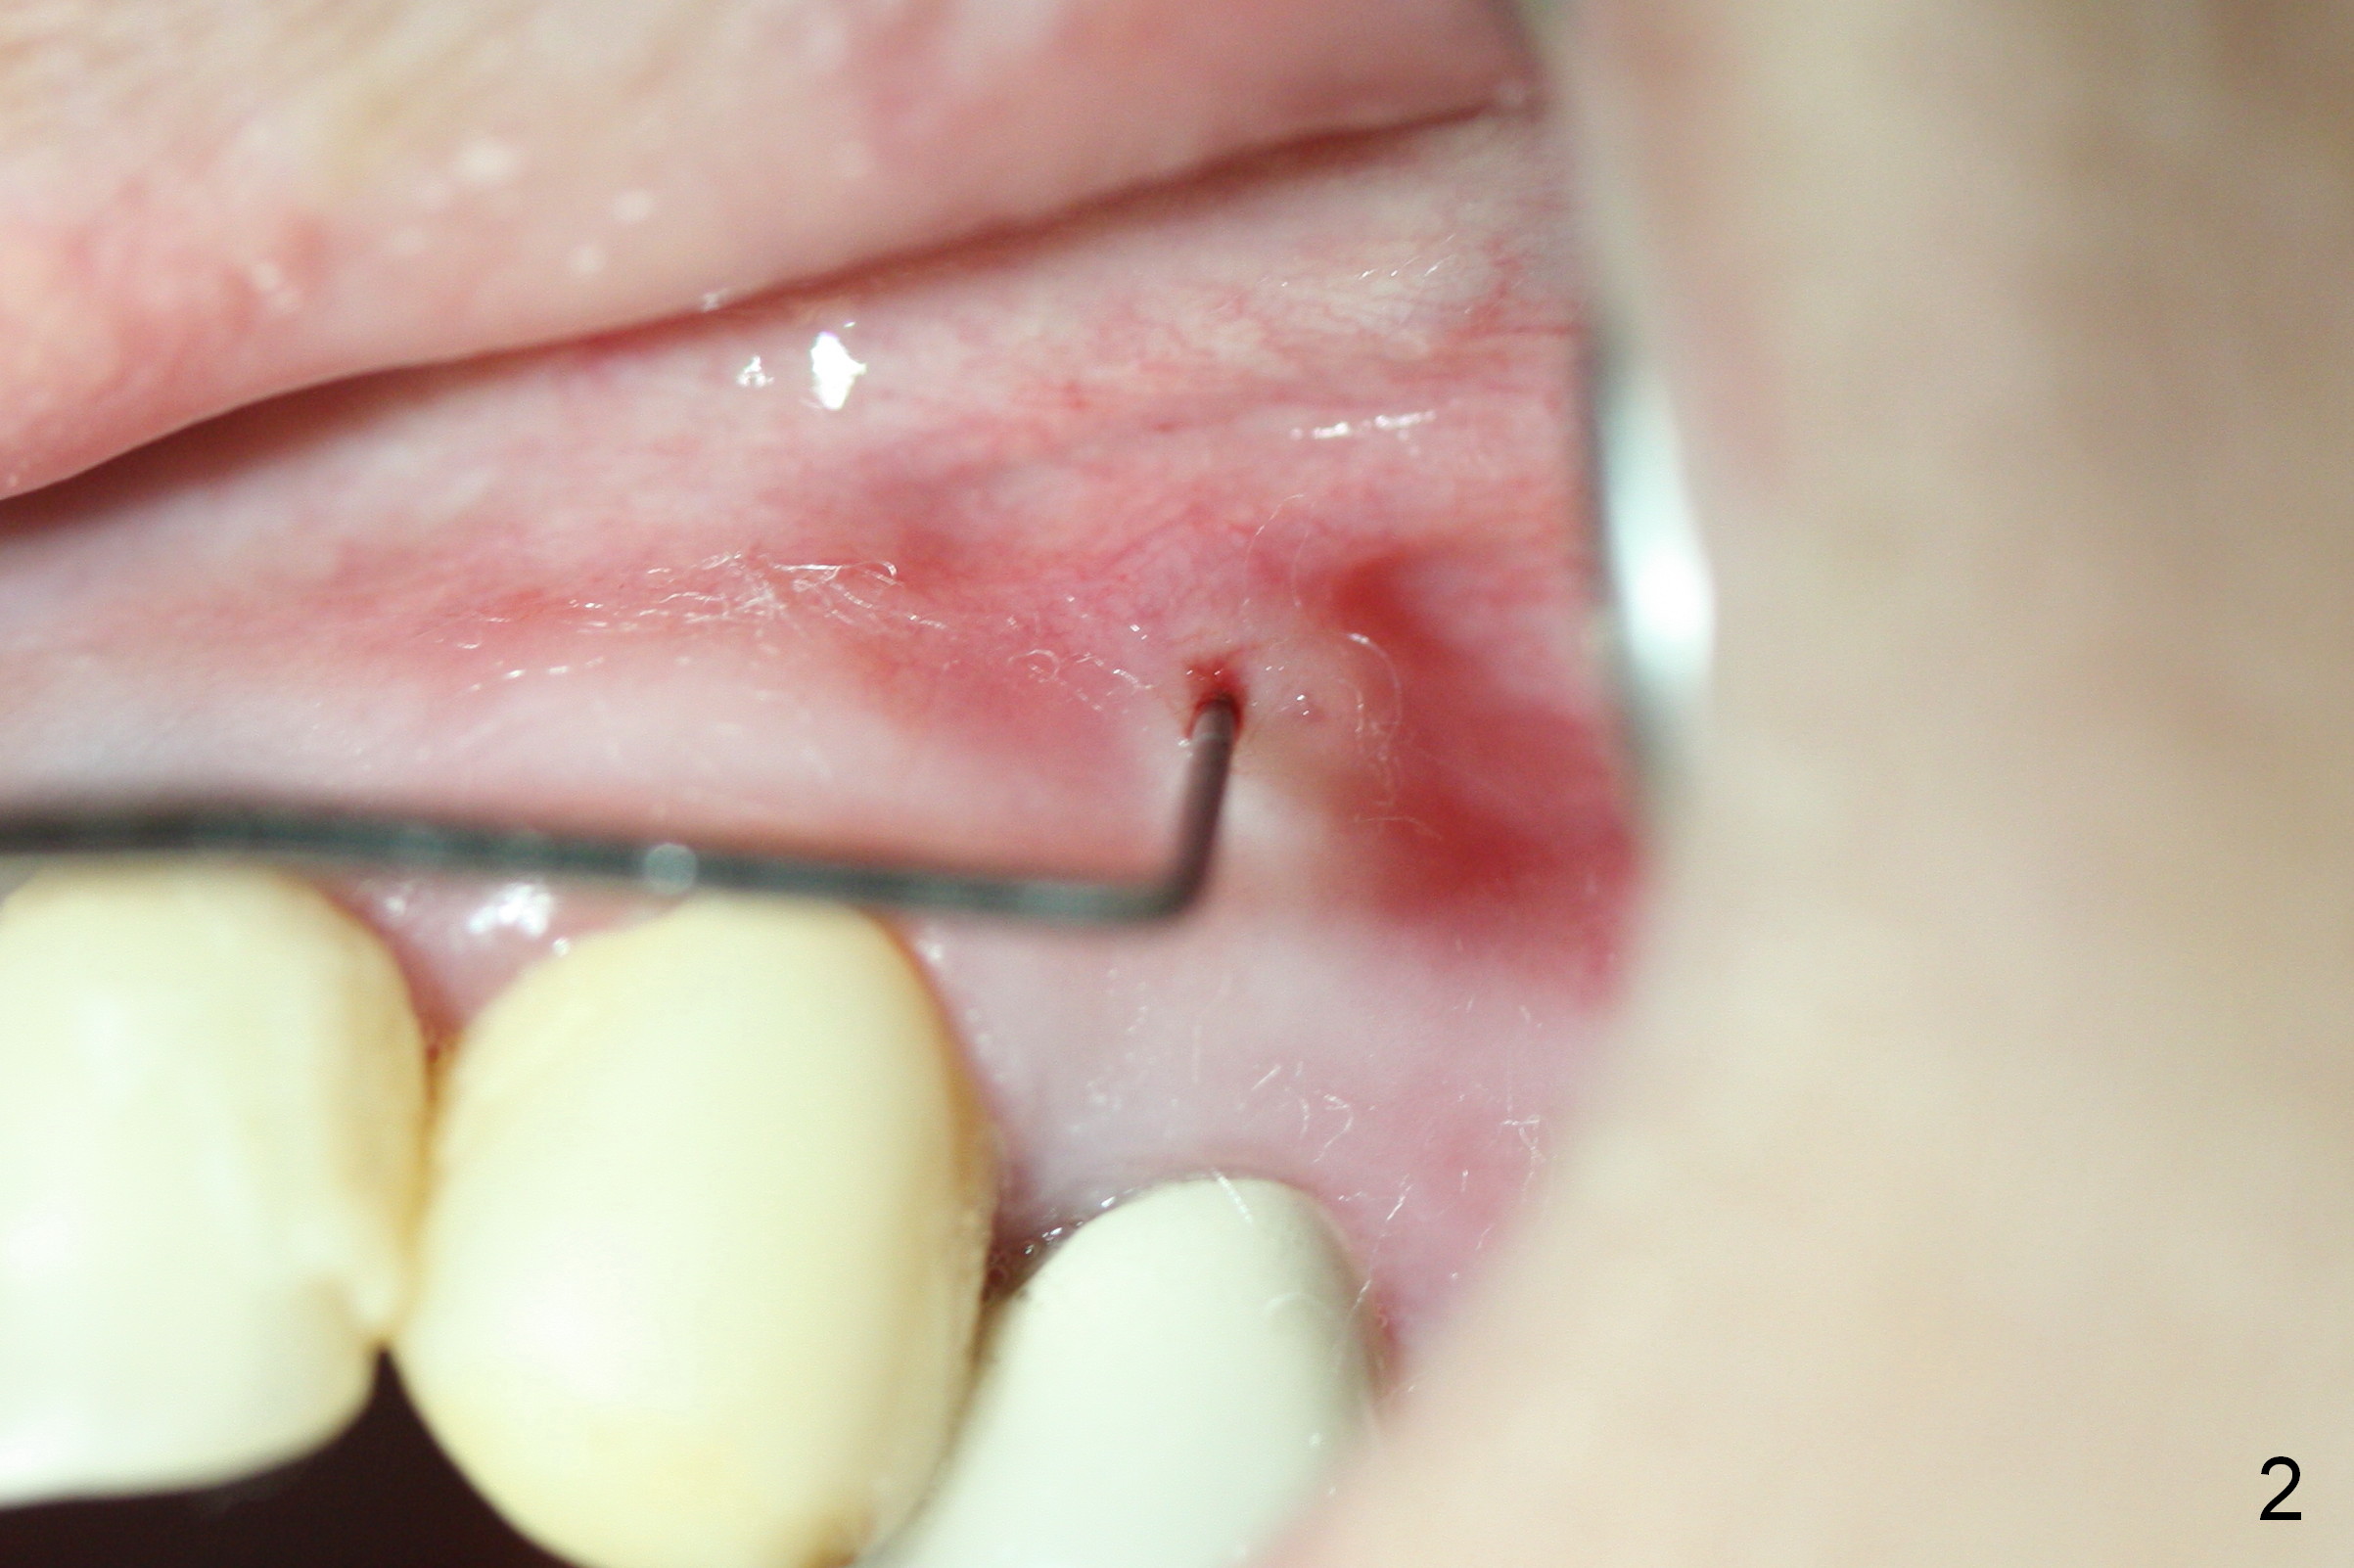

A 43-year-old woman has a persistent, asymptomatic fistula buccal to the tooth #12 (Fig.1,2). Prior to treatment, a #30 gutta percha is inserted into the fistula to confirm diagnosis (Fig.3). Hand files #15 and 20 are inserted to the buccal and lingual canals at 18 mm, respectively (Fig.4). Master cones (30/.04) are inserted buccally and lingually for 18 and 17 mm, respectively (Fig.5). There is minimal paste leakage after finishing RCT (Fig.6). Out of curiosity, the fistula is immediately curetted with removal of 2 small pieces of apparently leaked paste with minimal discomfort (total anesthetic: Xylocaine 34 mg, Epi 17 mcg). The fistula is expected to heal in 2 weeks.